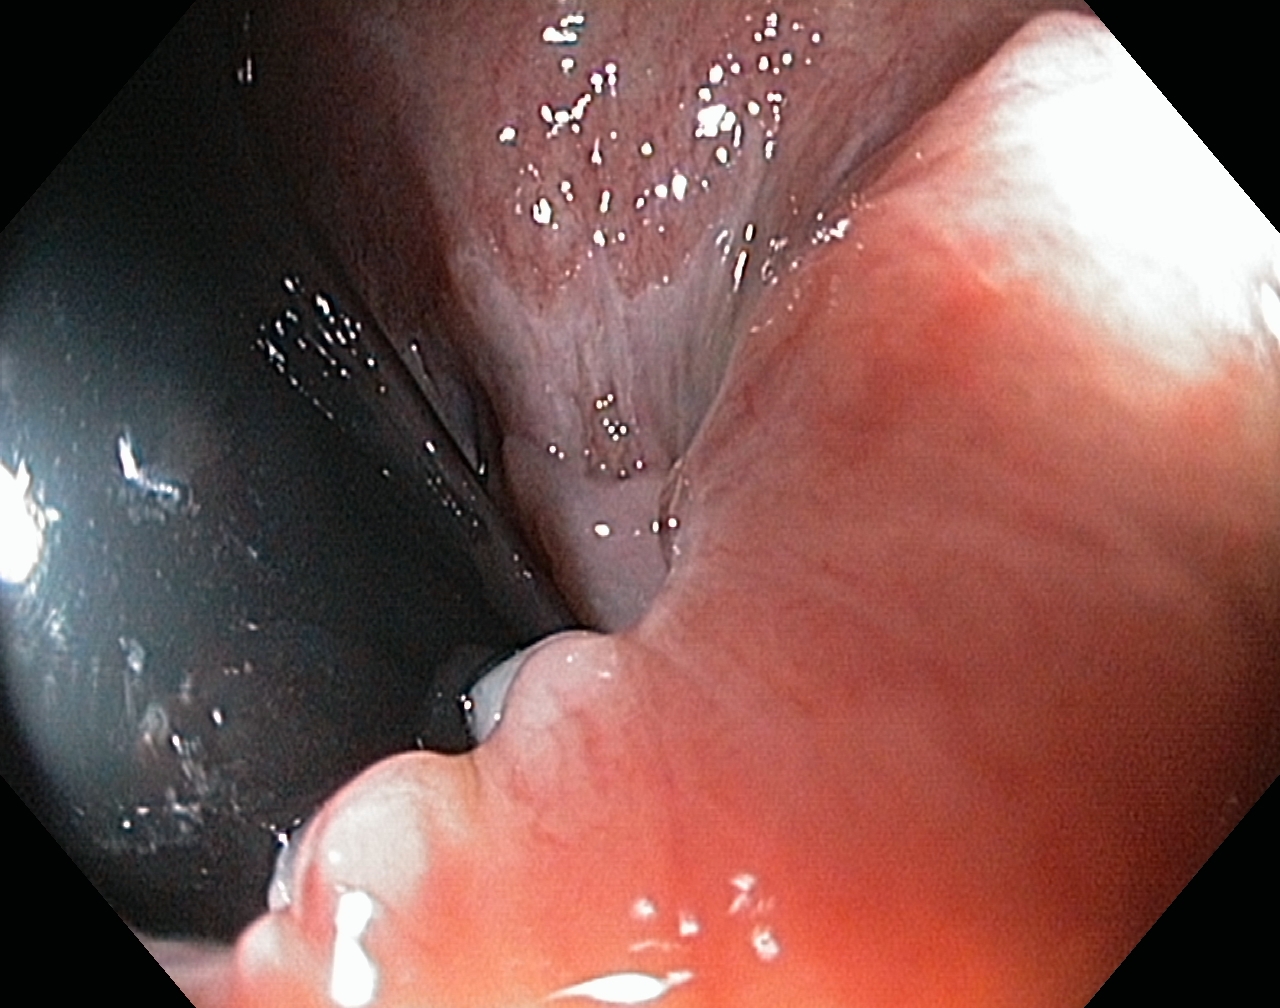

Linea dentata/anorectalis seen with the endoscope in an inverted position